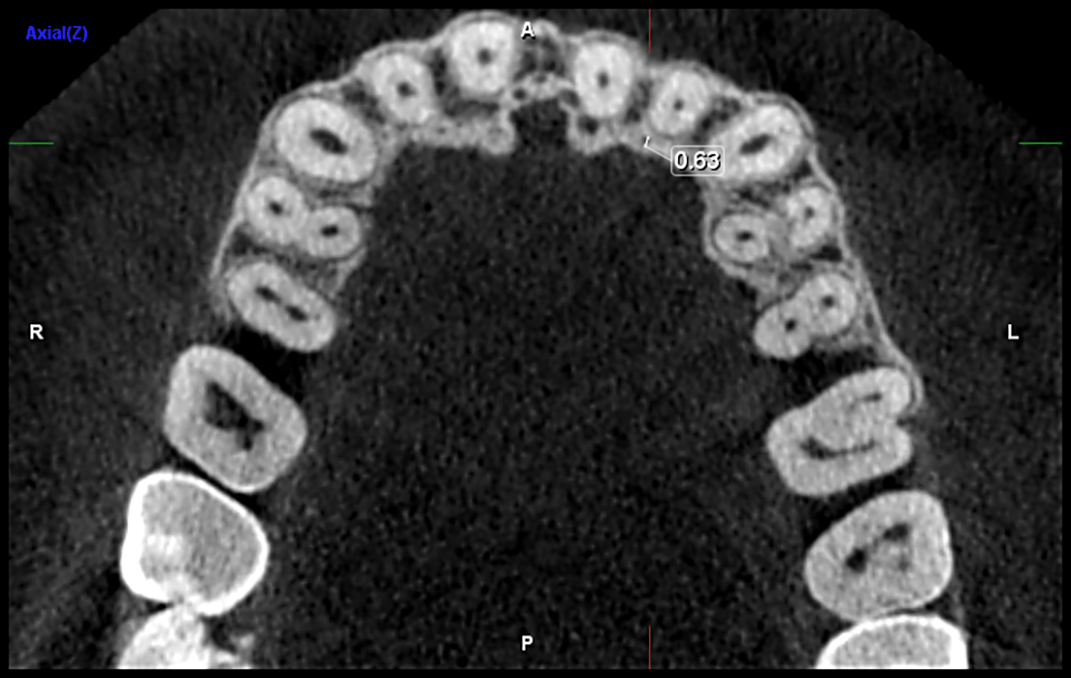

Diameter of the canal ( Figure 4)

The mean diameter of the CS near the alveolar crest was measured at 0.76 mm (±0.27) on the left side and 0.80 mm (±0.27) on the right side. The distance from the CS to the alveolar crest was recorded as 9.23 mm (±3.58) on the left side and 9.22 mm (±3.39) on the right side. The distance from the CS to the buccal cortical plate was 7.19 cm (±1.65), with a median of 7.18 cm, on the left side and 6.82 cm (±1.74) on the right side. Additionally, the distance from the CS to the floor of the nasal cavity was 11.4 cm (±3.78) on the left side and 11.6 cm (±3.64) on the right side ( Figure 5).

Diameter: The mean diameter of the CS is generally reported to be around 1 mm.14,19,20 However, in our study, we observed a mean diameter slightly less than 1 mm, which is consistent with the findings of Ghandourah AO et al.12 and Khojastepour L,15 although other studies have documented measurements exceeding 1 mm.4,5,21,22 While the precise relationship between canal diameter and the likelihood of complications remains uncertain, it is noteworthy that a larger neurovascular bundle may increase the risk of surgical issues, particularly bleeding. Furthermore, an increased canal diameter can potentially lead to misinterpretation of periapical lesions on standard radiographs.5